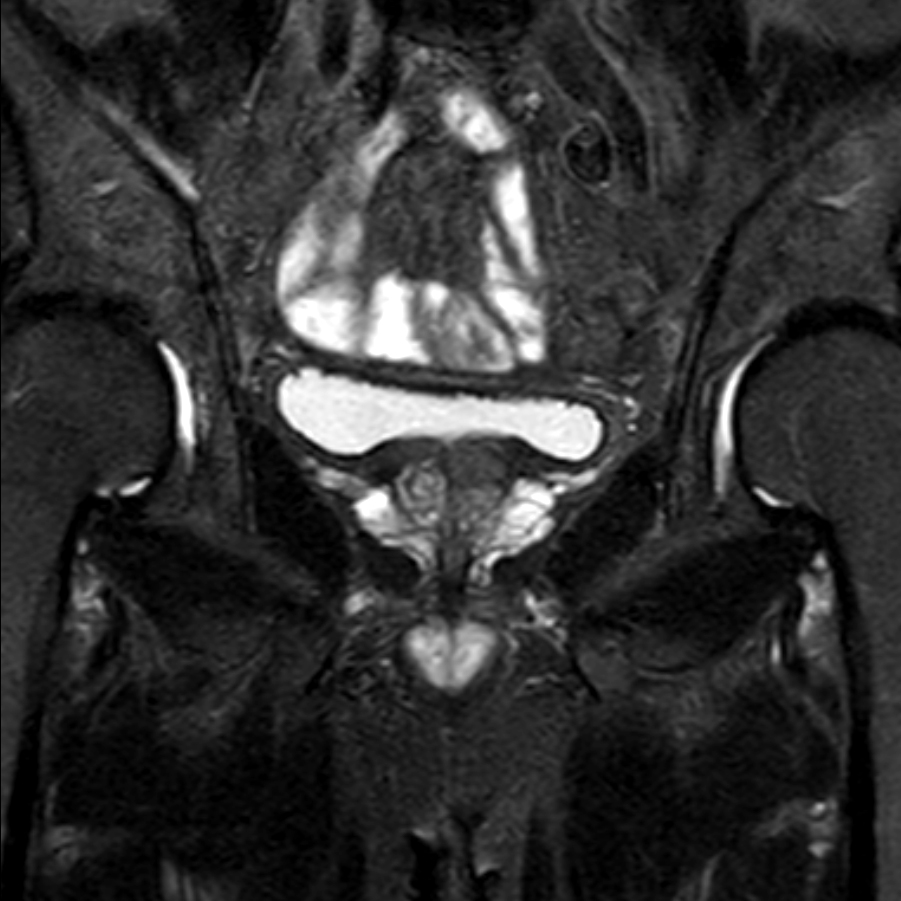

Coronal T2w TSE FatSat